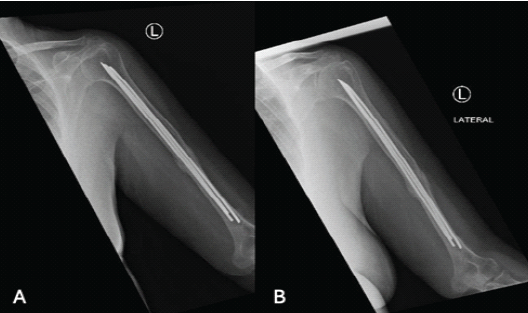

A 68-year-old right-hand dominant female presented after a fall with an isolated closed left spiral humerus fracture at the junction of the proximal ⅔ and distal ⅓ (Fig. 1).

Figure 1: Humerus fracture upon presentation after coaptation splint application, (a) showing anterior-posterior view, (b) showing lateral view.

The patient had no other injuries and was neurovascularly intact on presentation. She was an independent ambulator. The patient was treated with a coaptation splint in the emergency room, with plans for operative fixation the next day. Following a pre-operative assessment, the patient was scheduled for closed reduction with internal fixation under general anesthesia. In the supine position, with a radiolucent arm table, without a tourniquet. Landmarks were identified, and a 3–5 cm incision was taken from the lateral epicondyle. The lateral cortex was perforated with an awl, and entry was established and confirmed under fluoroscopy in both anteroposterior (AP) and lateral views. An adequate nail was then fixed in a universal chuck with a T-handle and advanced with oscillating hand movements until it reached the fracture site. The nail was introduced into the proximal fragment by indirect manipulation of the fragment under fluoroscopy. Subsequent manual advancement of the nail was carefully done, passing the fracture site until finally resting at the humeral head. Same steps were taken to reach a total of 3 elastic nails of size 3 mm filling the medullary canal. Following closure, the patient was placed in a functional brace with a non-weight-bearing (NWB) status of the left upper extremity (Fig. 2).

Figure 2: Humerus fracture post-fixation. (a) Anterior-posterior (AP) X-ray of the shoulder post-fixation, (b) lateral X-ray of the humerus post-fixation, (c) AP X-ray of the humerus post-fixation. (d) Lateral X-ray of the distal humerus post-fixation.